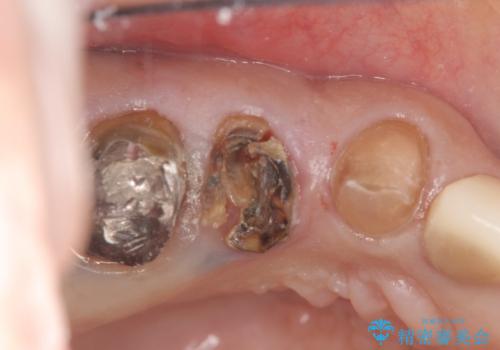

また単純に抜歯のみを行うと歯ぐきが大きく凹み、ブリッジの清掃性が損なわれることが予想されるため、抜歯時に歯槽堤保存術を行い

清掃性の高い仕上がりとなるよう配慮しています。